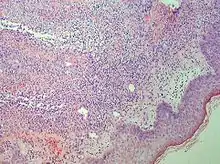

Studies show a moderate neutrophilia (less than 50%), elevated ESR (greater than 30 mm/h) (90%), and a slight increase in alkaline phosphatase (83%). Skin biopsy shows a papillary and mid-dermal mixed infiltrate of polymorphonuclear leukocytes with nuclear fragmentation and histiocytic cells. The infiltrate is predominantly perivascular with endothelial-cell swelling in some vessels, but vasculitic changes (blood clots; deposition of fibrin, complement, or immunoglobulins within the vessel walls; red blood cell extravasation;inflammatory infiltration of vascular walls) are absent in early lesions.Perivasculitis occurs secondarily, because of cytokines released by the lesional neutrophils. True transmural vasculitis is not an expected finding histopathologically in SS.